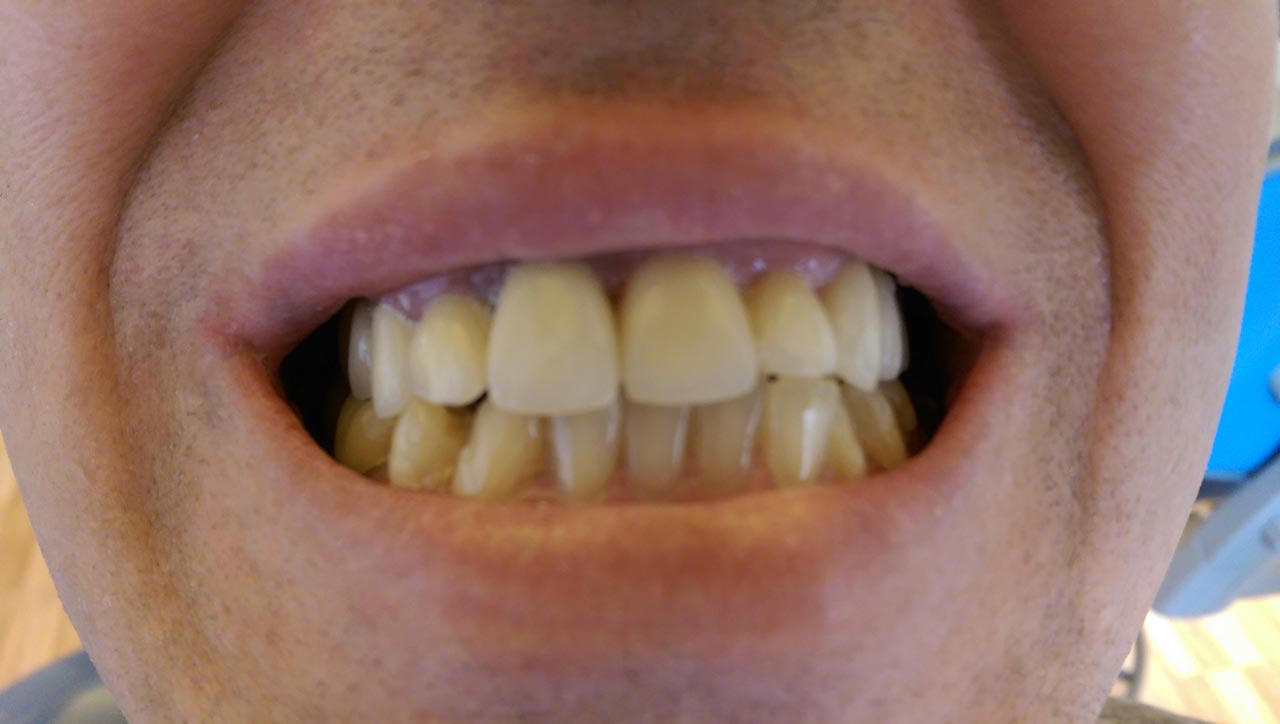

Teljes fogatlanság helyreállítása 2 nap alatt

Teljes fogatlanság helyreállítása 2 nap alatt azonnal terhelhető svájci IHDE implantátumokkal és PMMA műanyag hidakkal. Intraorális szkennerrel vettünk lenyomatot az implantáció után, és erre a digitális mintára készítette el a fogtechnika a hidak digitális tervezését, majd faragta ki műanyagból. Ezt a gyors munkát az azonnal terhelhető implantátumok és a digitális lenyomat, tervezés segítségével tudtuk megcsinálni mindössze 2 nap alatt. Dr. Kelemen Péter és a Symbion Fogtechnika munkája.